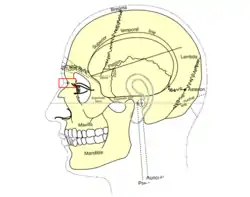

Side view of head, showing surface relations of bones. (Nasion labeled at center left.) | |

The nasion (/ˈneɪziɒn/) is the most anterior point of the frontonasal suture that joins the nasal part of the frontal bone and the nasal bones. It marks the midpoint at the intersection of the frontonasal suture with the internasal suture joining the nasal bones.[1] It is visible on the face as a distinctly depressed area directly between the eyes, just superior to the bridge of the nose. It is a cephalometric landmark that is just below the glabella.[2]